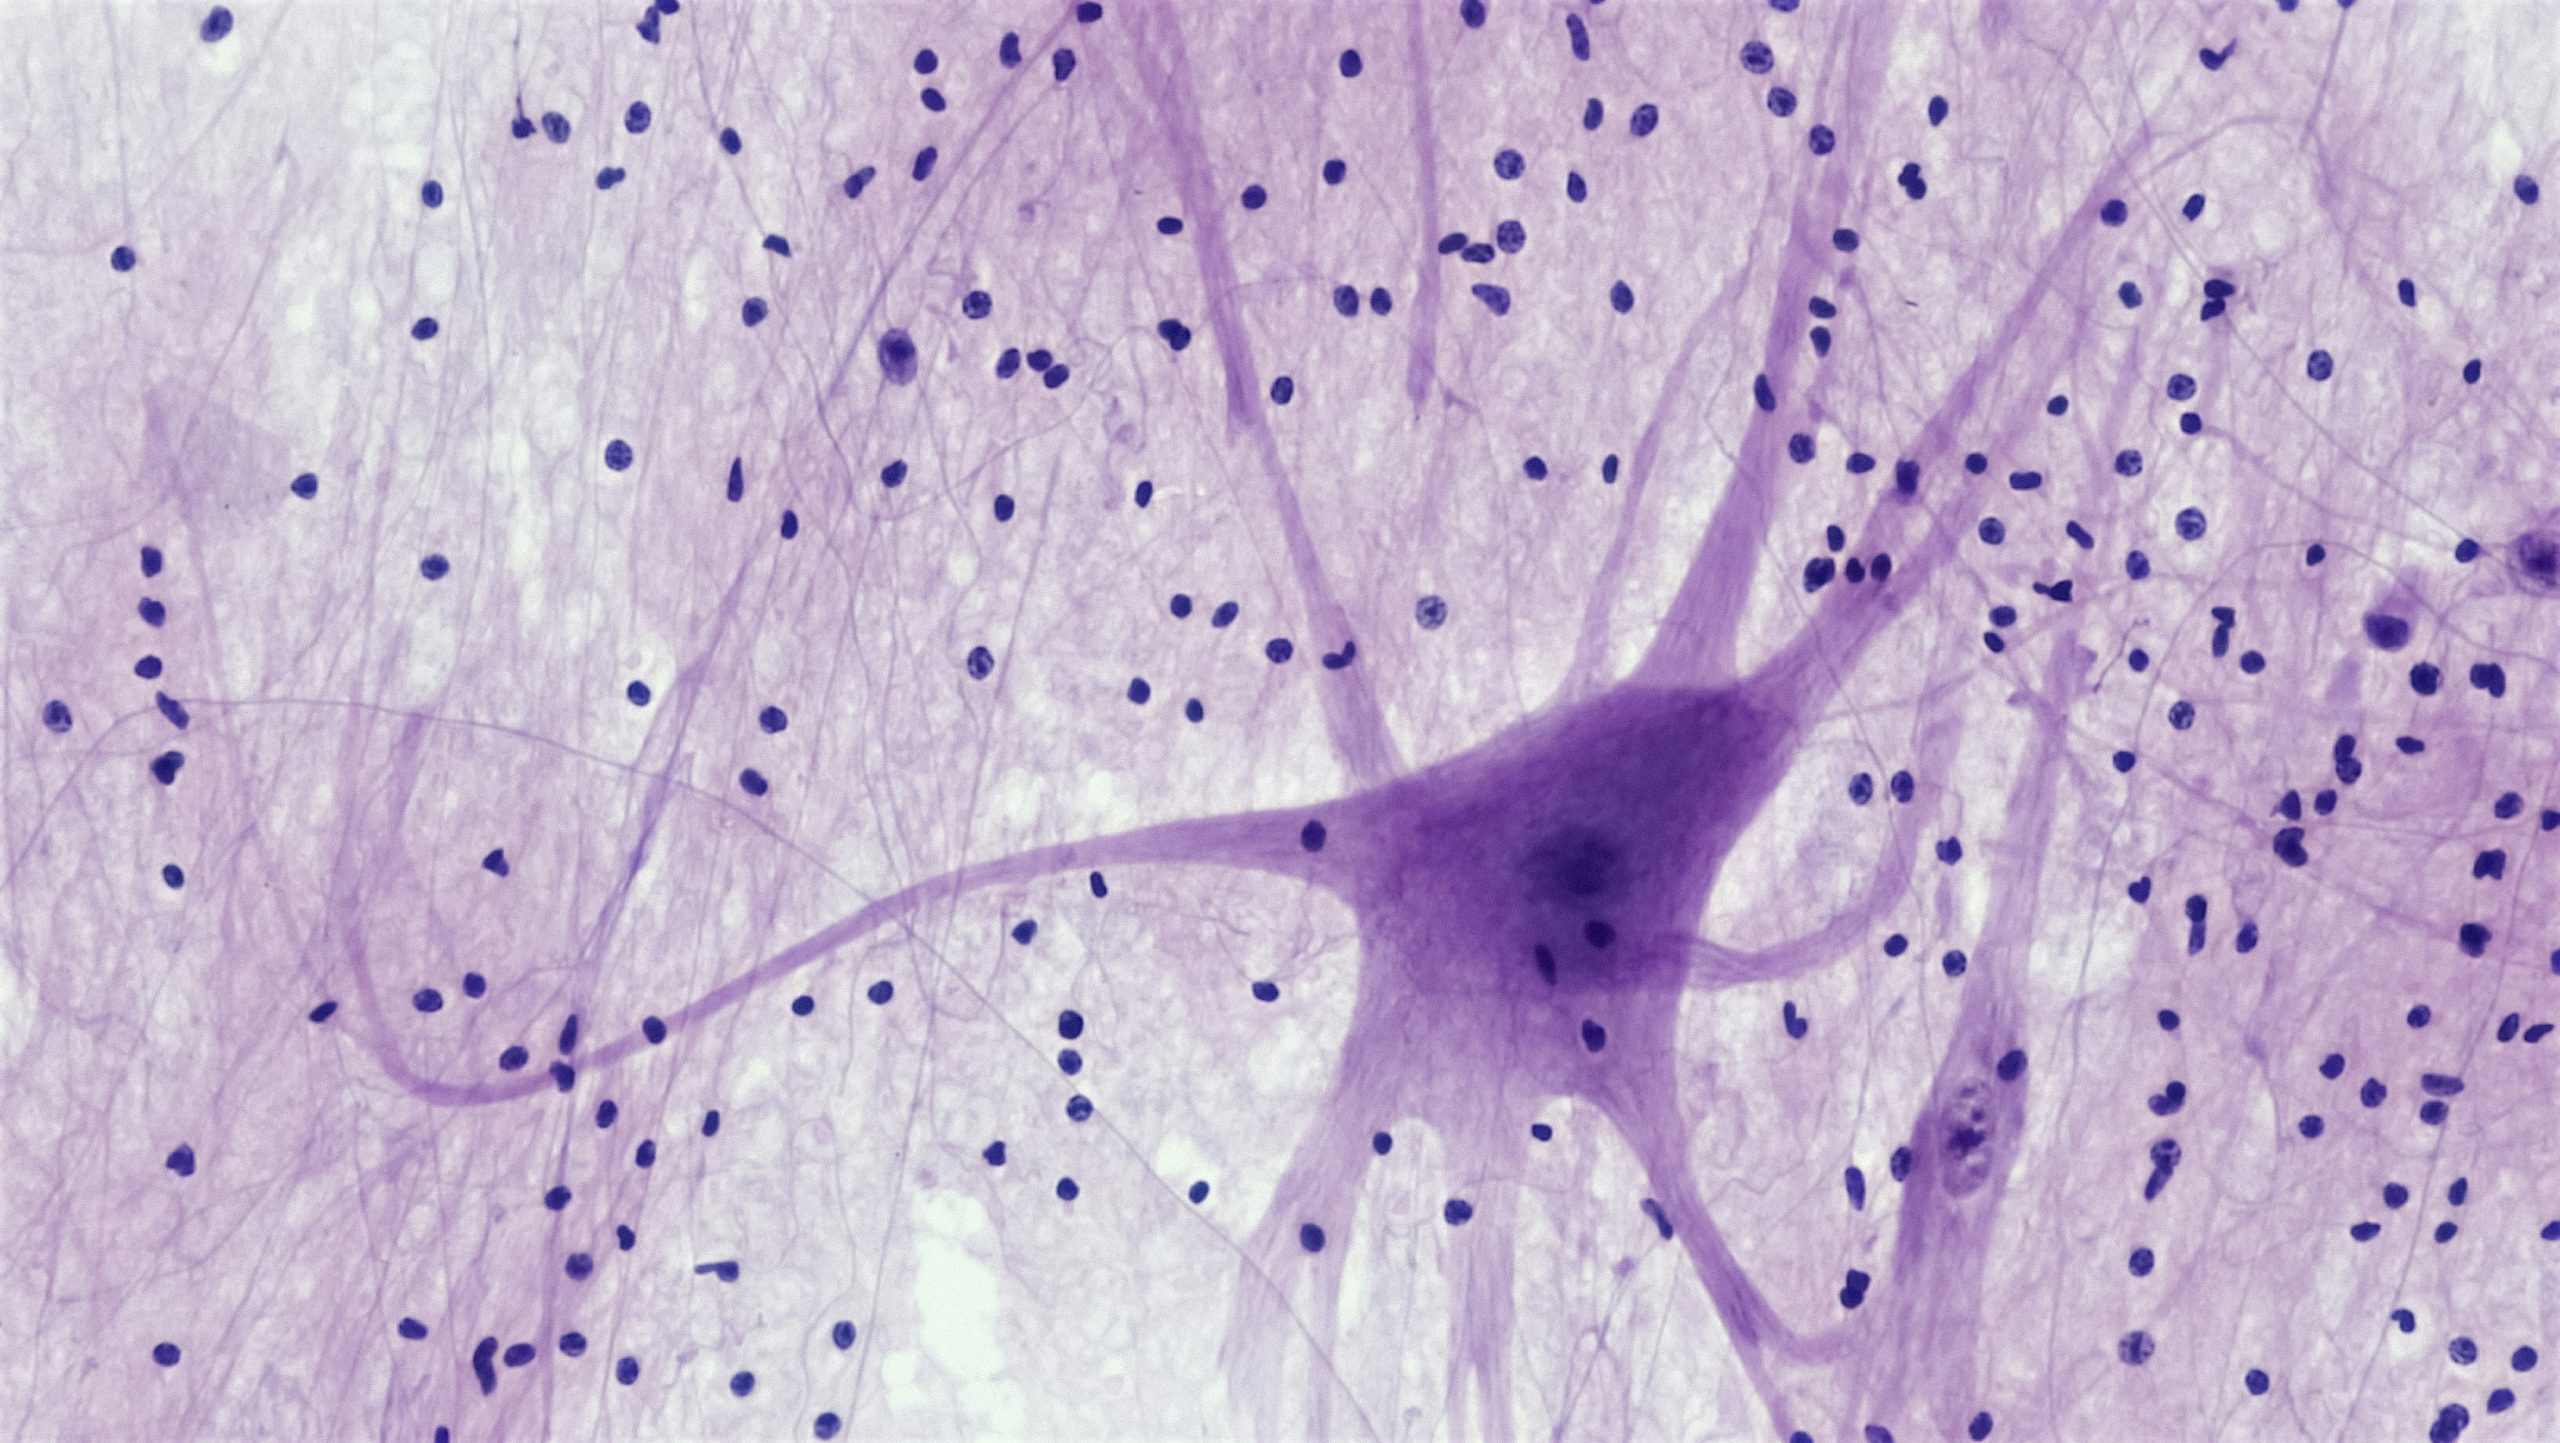

Hi! My name is Anna Moyer, and I’m the creator of Accessible Chef. I started this project over ten years ago as a way to teach cooking skills to people with intellectual disabilities, and I’m thrilled that life skills teachers, therapists, and other disability advocates and self-advocates are still using the resources today. Although I started the project while I was in high school, inspired by my brother Sam, I’m now a postdoctoral researcher in Dr. Summer Thyme’s lab studying how the brain develops in people with Down syndrome. Improving Accessible Chef is a side project for me, but feel free to contact me at anna.moyer@gmail.com with questions, comments, or requests.